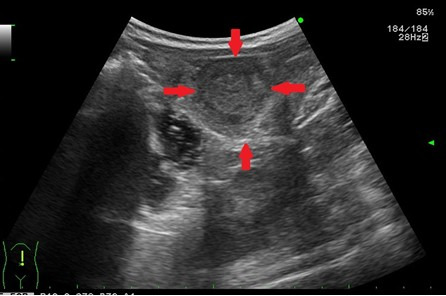

- 간경화